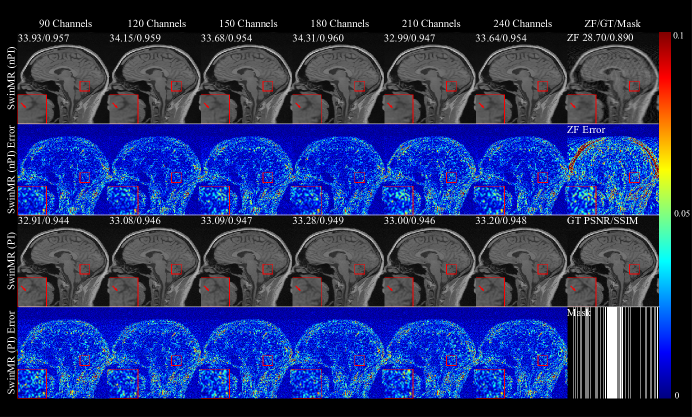

Figure 13 (B) and Figure 13 (D) show the SSIM, PSNR and FID of SwinMR with different channel numbers. Figure 13 (F) shows the loss function of SwinMR in the training process. Figure 15 displays the sample of reconstructed images of SwinMR with the different channel numbers.

For the channel number, from Figure 13 (B) and Figure 13 (D), the results did not resemble the trend presented in the ablation experiment on patch number. There were no significant differences for the three metrics (SSIM, PSNR and FID) as the channel number changed. According to Figure 13 (F), the training loss converges faster and lower as the channel number grows. Empirically, we applied a channel number of 180 for training.

Refer to caption

Figure 15: Samples of the ablation experiment on the channel number using Gaussian 1D 30% mask. Row 1: Reconstructed MR images by SwinMR (nPI) with the different channel numbers and zero-filled MR images (ZF); Row 2: Absolute differences (10×10\times) between reconstructed MR images by SwinMR (nPI) and ground truth MR images (GT), and absolute differences (10×10\times) between ZF and GT; Row 3: Reconstructed MR images by SwinMR (PI) with the different channel number and GT; Row 4: Absolute differences (10×10\times) between reconstructed MR images by SwinMR (PI) and GT, and the Gaussian 1D 30% mask.